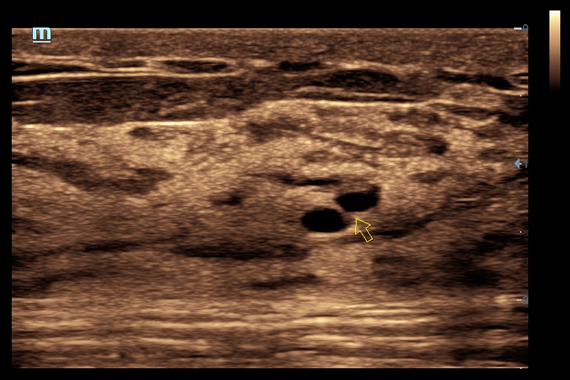

• iNeedle™ - улучшенная визуализация игл при проведении биопсии линейными датчиками